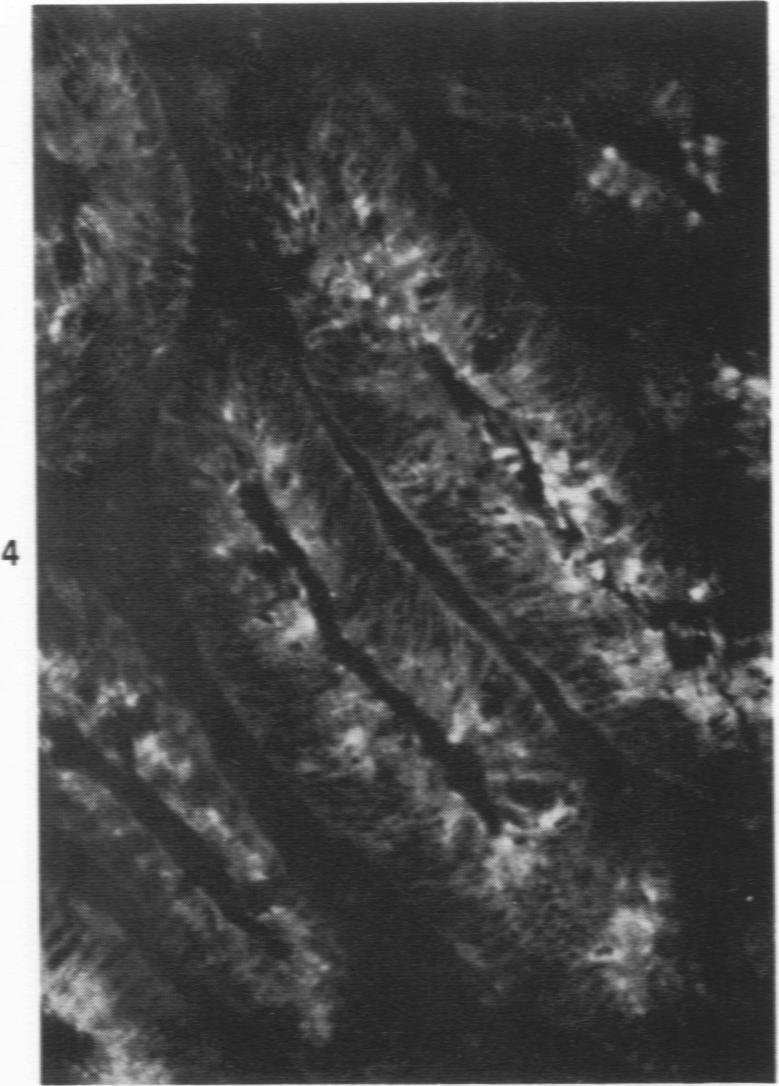

The secretory component (SC) polypeptide chain of secretory immunoglobulin A can be considered as a differentiation marker in that it is normally synthesized in the non-mucus-containing columnar epithelial cells, but not goblet cells, of the large intestine. With this in mind, we have studied the expression of SC in 36 colonic adenocarcinomas and 15 polyps (adenomatous and villous) by the fluorescent antibody technique. As in the normal mucosa, the synthesis of SC in tumors found in non-mucus-containing columnar cells and was absent from goblet cells. However, in several well-differentiated carcinomas it appeared that columnar cells contained both SC and mucin; these cells could be analogous to the normal mucosal precursor of both cell types. SC was synthesized throughout all adenomatous polyps and villous adenomas with the exception of some atypical nonmucinous areas of adenomatous polyps. Secretory component synthesis by carcinomas was associated with mucus production, although goblet cells did not contain SC. The presence of SC also correlated with the degree of differentiation. Secretory component was absent from half of the carcinomas as well as from atypical nonmucinous areas of polyps, and this could represent one of the earliest changes associated with the development of malignancy.

分泌型免疫球蛋白A的分泌成分(SC)多肽链可被视为一种分化标志物,因为它通常在大肠不含黏液的柱状上皮细胞而非杯状细胞中合成。基于此,我们采用荧光抗体技术研究了36例结肠腺癌和15例息肉(腺瘤性和绒毛状)中SC的表达情况。与正常黏膜一样,在不含黏液的柱状细胞中发现肿瘤能合成SC,而杯状细胞中则没有。然而,在一些高分化癌中,柱状细胞似乎同时含有SC和黏蛋白;这些细胞可能类似于这两种细胞类型的正常黏膜前体细胞。除了腺瘤性息肉的一些非典型非黏液区域外,所有腺瘤性息肉和绒毛状腺瘤均能合成SC。癌组织合成SC与黏液产生有关,尽管杯状细胞不含SC。SC的存在也与分化程度相关。一半的癌组织以及息肉的非典型非黏液区域均未检测到SC,这可能是与恶性肿瘤发生相关的最早变化之一。